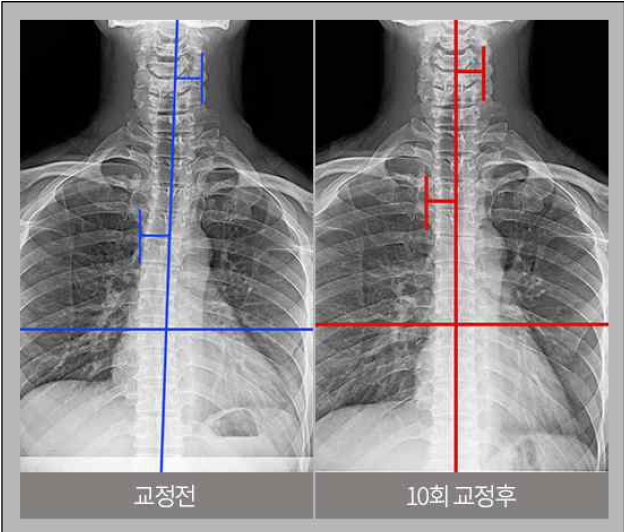

<이미지2: 척추 교정 전·후 비교 사진>

[출처: 리봄한방병원 홈페이지]